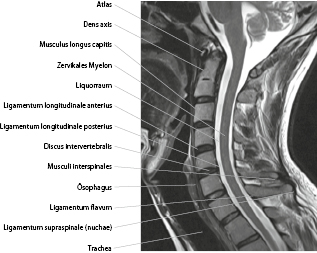

Ligamentum longitudinale posterius. It narrows to pass between the pedicles and spreads out to blend with the outer lamellae of the posterior aspect of the anulus fibrosus of the intervertebral discs;. The Posterior Longitudinal Ligament (ligamentum longitudinale posterius;. Posterior common ligament) (Figs 301, 302) —The posterior longitudinal ligament is situated within the vertebral canal, and extends along the posterior surfaces of the bodies of the vertebræ, from the body of the axis, where it is continuous with the membrana tectoria.

Ligamentum longitudinale posterius Processus spinosus Lamina arcus vertebrae Processus transversus Ligamenta intertransversaria Capsula articulationis zygapophysiales Ligamentum supraspinale Ligamentum sacroiliacum posterius Ligamentum iliolumbale B Posterior view _CH01qxd 3/28/08 1005 AM Page 14. Posterior common ligament) (Figs 301, 302) —The posterior longitudinal ligament is situated within the vertebral canal, and extends along the posterior surfaces of the bodies of the vertebræ, from the body of the axis, where it is continuous with the membrana tectoria, to the sacrum. Ligamentum cruciatum posterius Silný zadní zkřížený vaz kolenní se táhne anterolaterálně z povrchu mediálního kondylu femuru, postupuje posteriorně a inferiorně oblastí mezi kondylami a upevňuje se zezadu na interkondylární oblast tibia ligamentum cruciatum – zkřížený vaz v koleně.

Zusammenfassung Die Verknöcherung des Ligamentum longitudinale posterius (OPLL) in Kombination mit der Verknöcherung des Ligamentum flavum (OYL) am Brustwirbel, die als eine Erkrankung der Wirbelkanalhyperostose genannt wird, kann schwere Myelopathie verursachen, die zur SandwichAbdrückung des Rückenmarks von der Vorder und Rückseite aus kommt. Other Terms Ligamentum longitudinale posterius, Ligament longitudinal postérieur Parts None Group Vertebral ligaments Description Forming the anterior wall of the vertebral canal, this strong ligament spans from the body of the axis (C2) to the posterior surface of the sacrum. Pos·te·ri·or lon·gi·tu·di·nal lig·a·ment TA the fibrous band interconnecting the posterior surfaces of the vertebral bodies;.